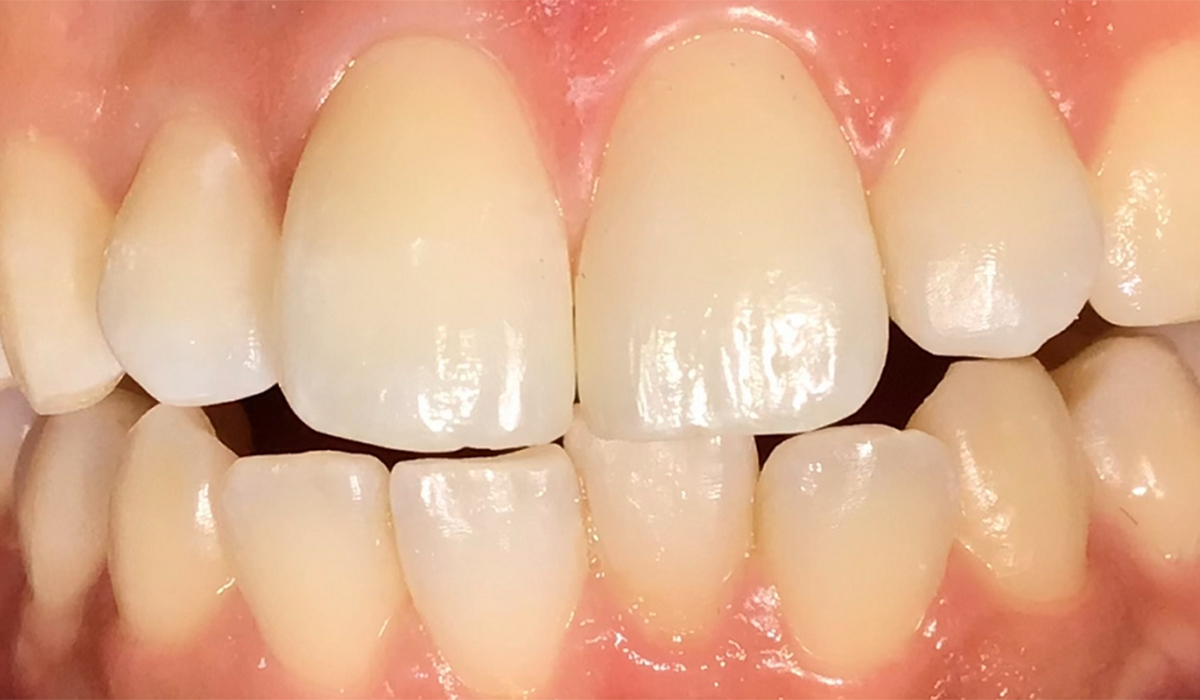

- 前歯のすきっ歯

歯と歯の間の隙間をダイレクトボンディングで自然な見た目に修復しています。